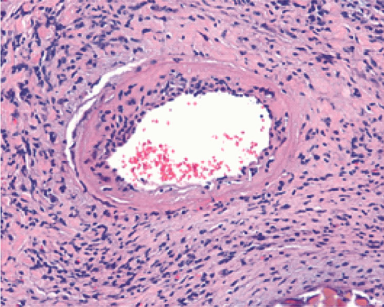

Heart transplant

In a clinical-translational approach we aim to examine primary cardiac graft quality via tissue and circulating biomarker analyses in different preservation technologies in human heart transplant patients. The HTX research team seeks to improve current preservation strategies by assessing the effects of hypo- and normothermic pulsatile machine perfusion on donor heart function.